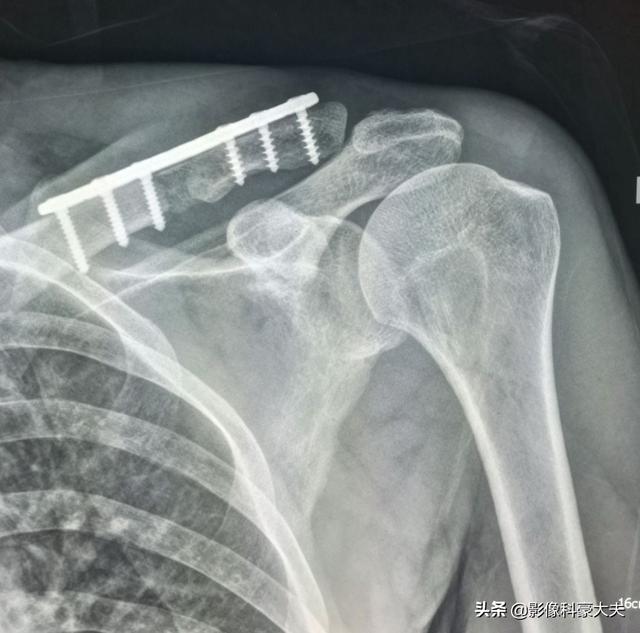

Métastase claviculaire d'un carcinome peu différencié ayant survécu à la tumeur pendant 5 ans.

Il s'agit d'un homosexuel de 58 ans qui a commencé à ressentir une douleur persistante lorsque son épaule a été légèrement étirée, et les radiographies ont révélé des foyers hypodenses :

Il s'agissait d'une fracture pathologique causée par des forces externes mineures sur la base d'une métastase osseuse. Une ponction a été effectuée et la pathologie était une métastase osseuse d'un adénocarcinome pulmonaire peu différencié.

Il s'agit de l'opération de fixation interne qu'il avait réalisée à l'époque pour une fracture de la clavicule, une fracture pathologique qui a beaucoup de mal à guérir seule sans intervention chirurgicale.